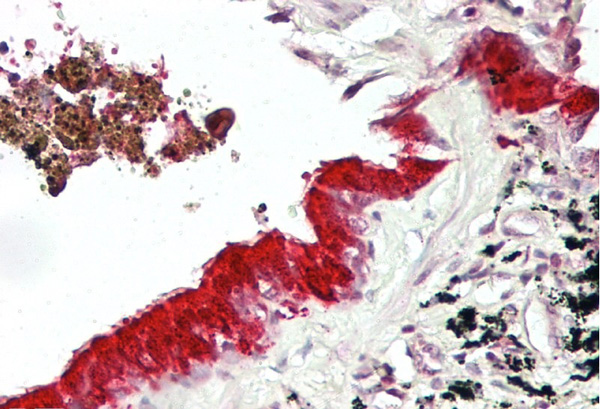

IHC (Immunohiostchemistry)

(Rabbit Anti-MXI1 AntibodyParaffin Embedded Tissue: Human LungCellular Data: Epithelial cells of bronchioleAntibody Concentration: 4.0-8.0 ug/mlMagnification: 400X)

IHC (Immunohistochemistry)

(IHC Suggested Anti-MXI1 antibodyTitration: 5ug/ mlPositive Control: Lung, respiratory epithelium)